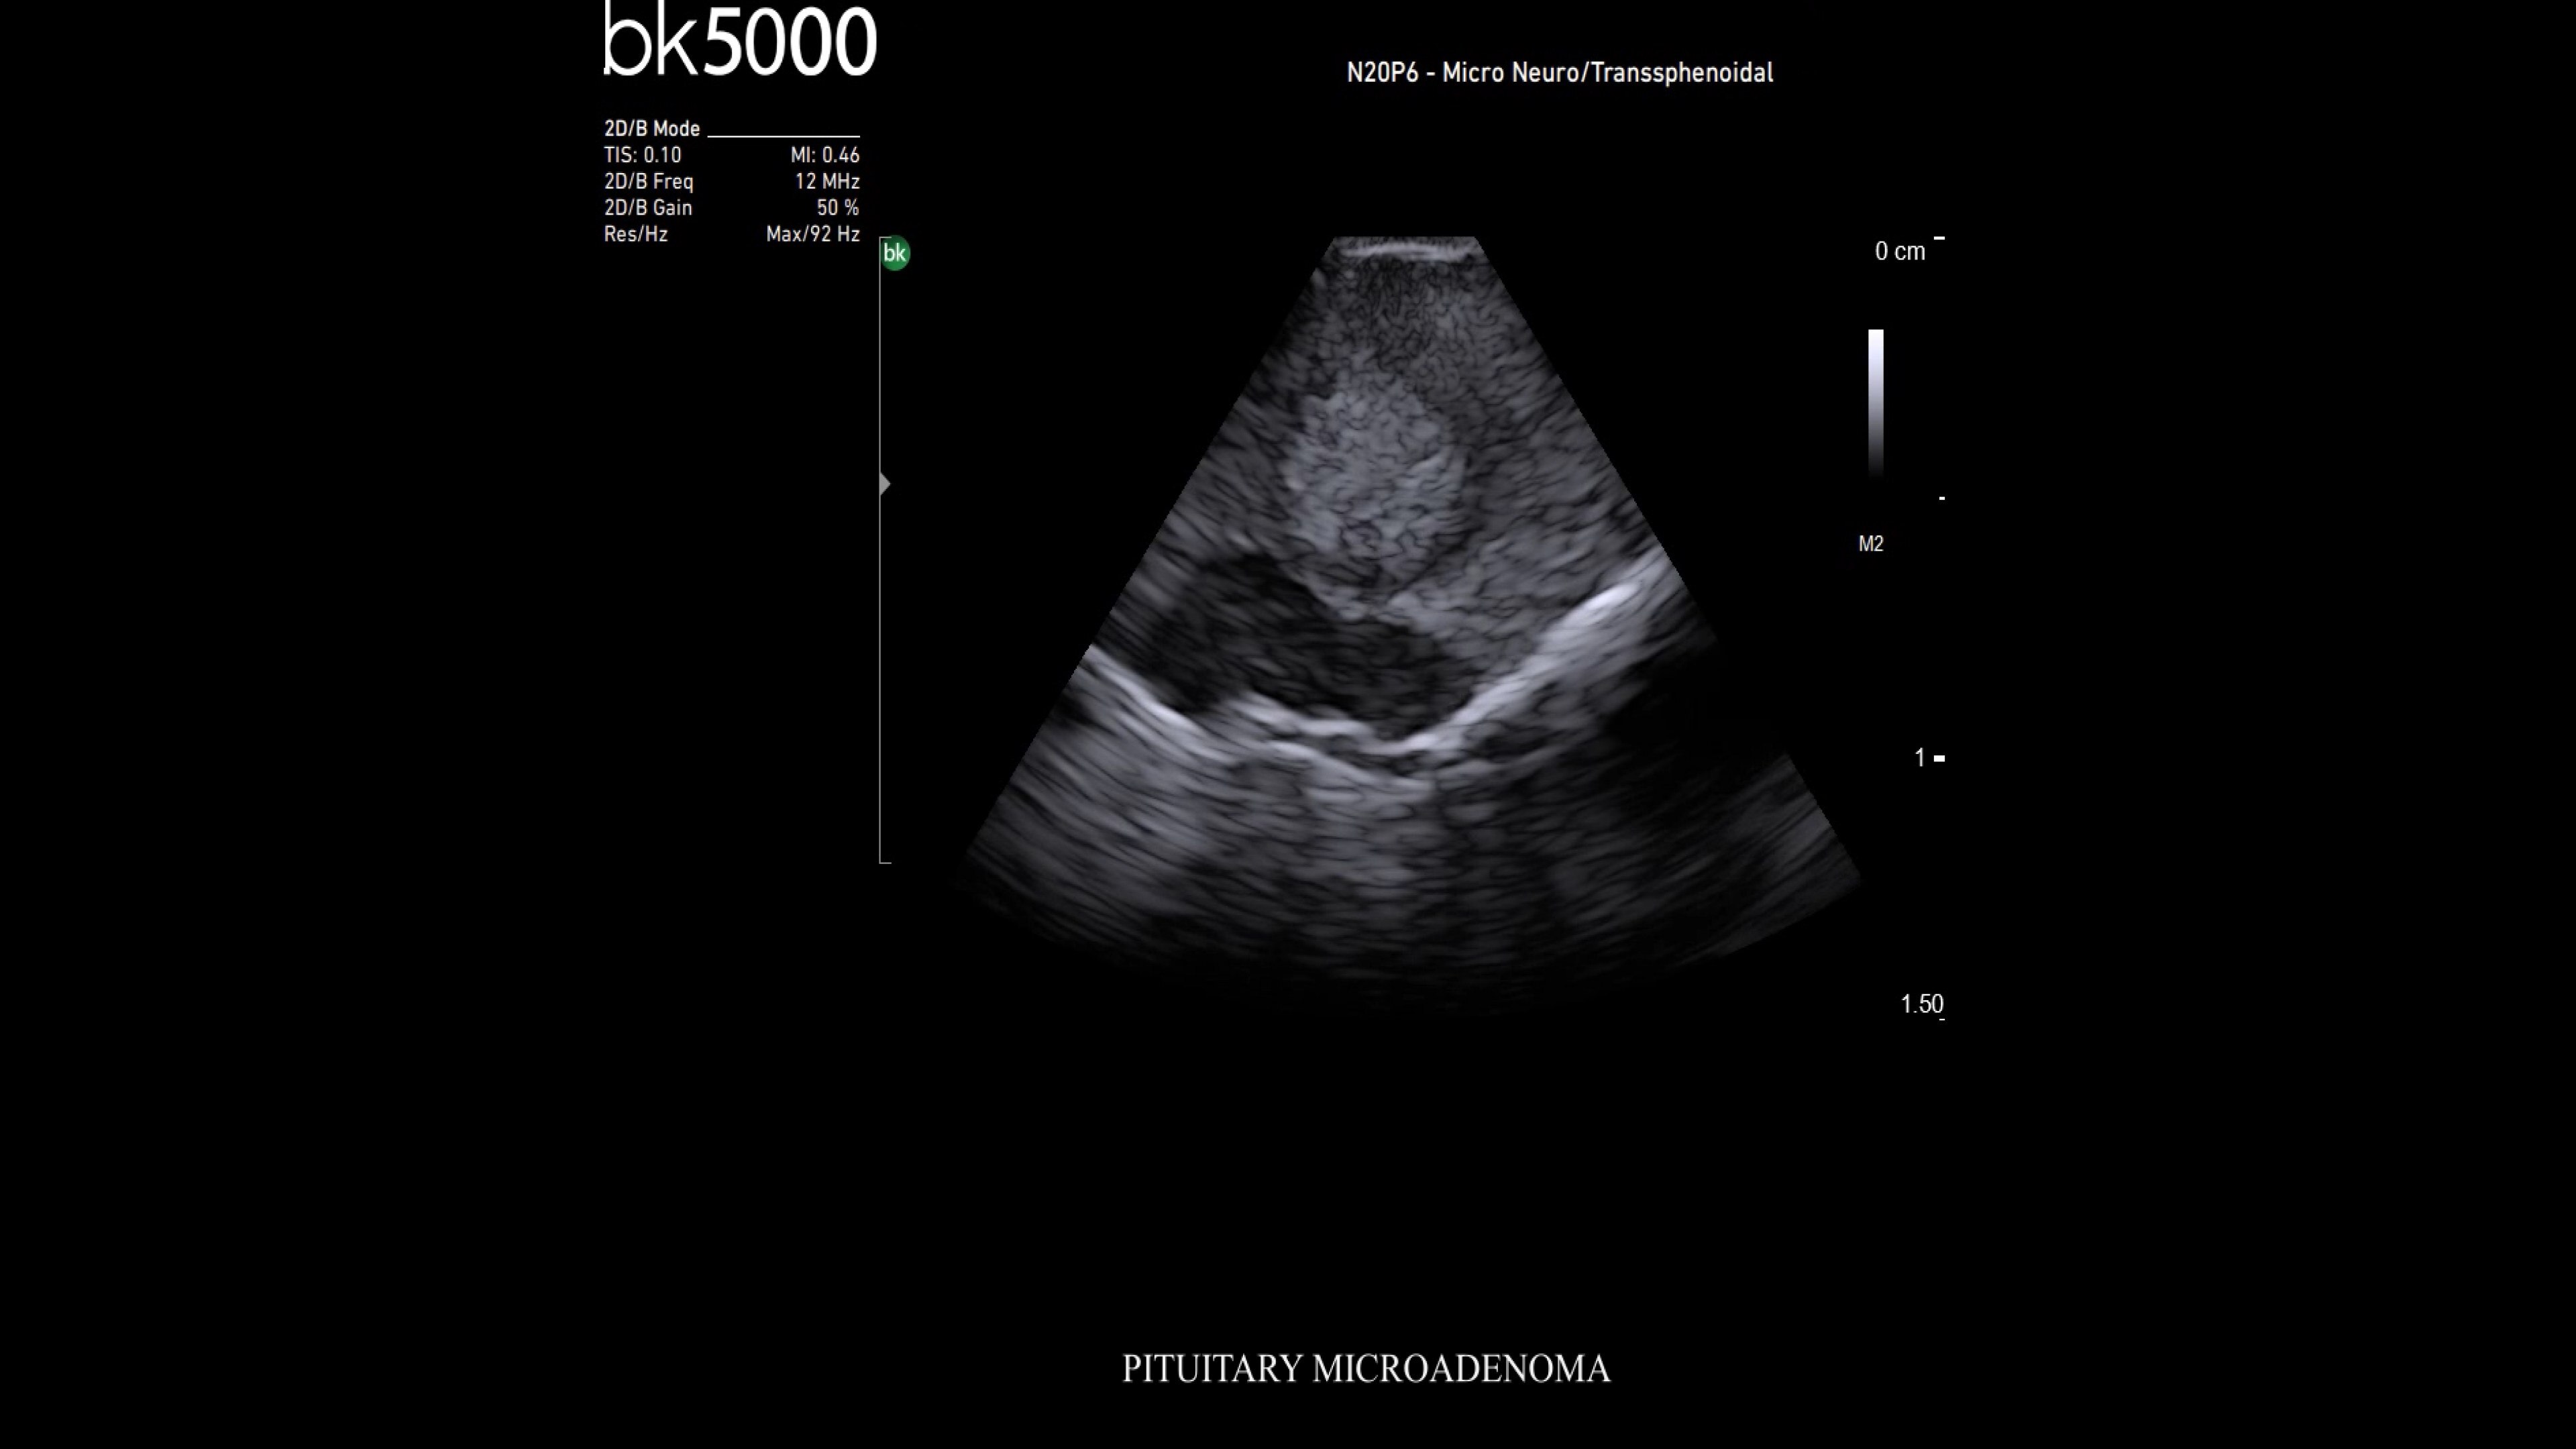

Neurosurgery

Premium ultrasound imaging in neurosurgical procedures

Ultrasound enhances neurosurgery by providing real-time navigation and lesion identification, crucial as preoperative CT/MRI data can be outdated. The bk5000 system offers high-quality images to see lesion margins and determine actions. Advanced graphics processing ensures immediate, auto-optimized images.

• Neurosurgery transducers: High-resolution, sterilizable transducers provide detailed brain and spinal cord images. The Smart™ button allows easy activation, freezing, storing, or printing of images. Disposable needle guides aid lesion targeting.